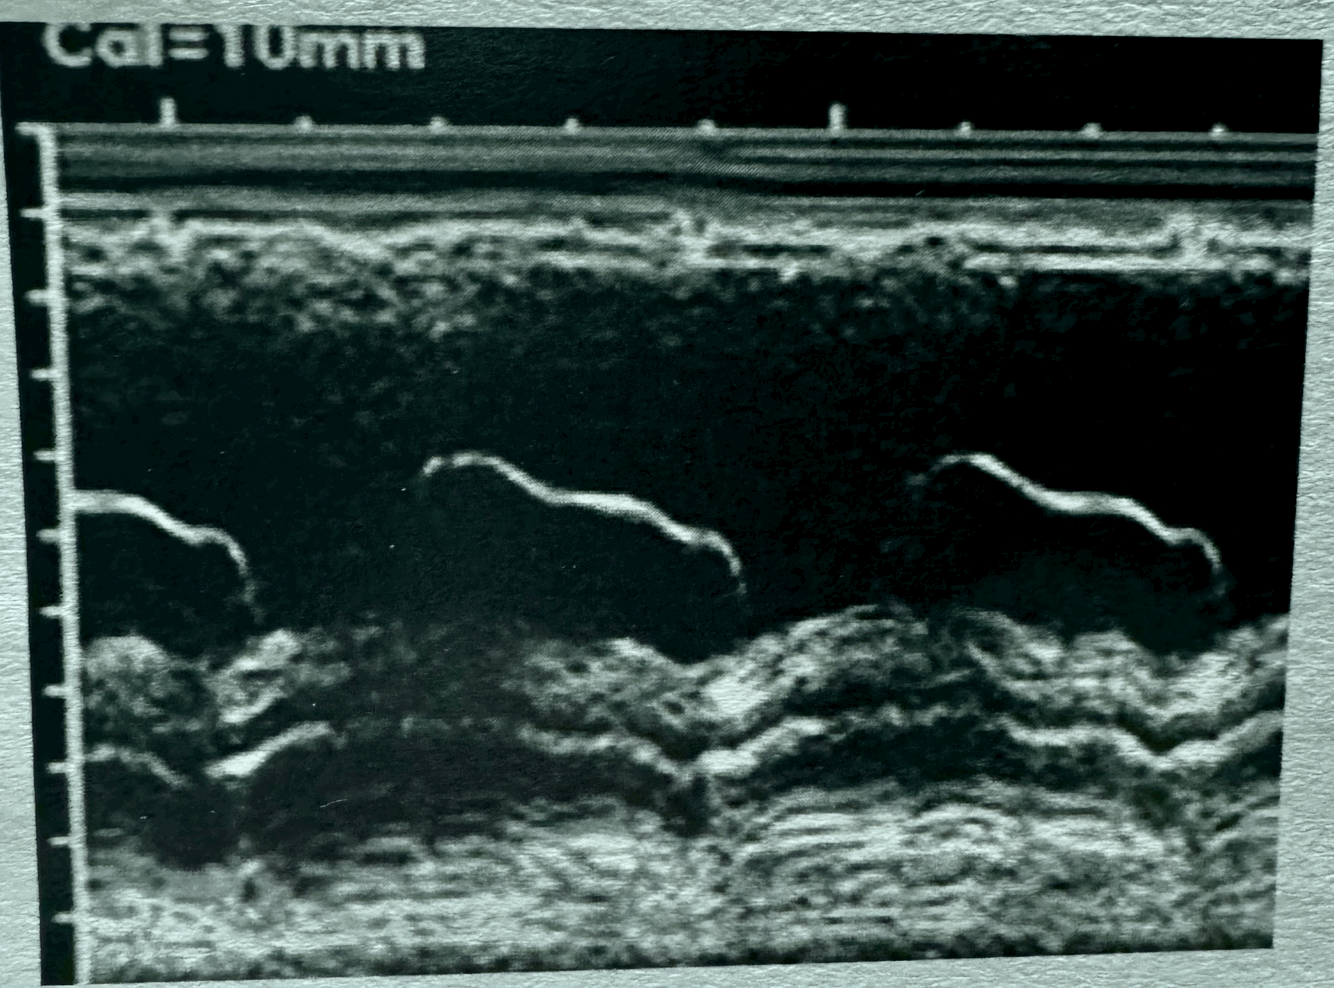

What is this M-mode showing?

17